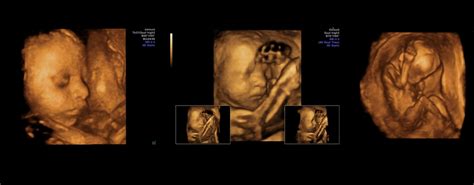

Rolul Ecografiilor în Monitorizarea Sarcinii

Ecografiile reprezintă o componentă esențială a monitorizării prenatale, oferind informații vitale despre dezvoltarea fătului și sănătatea sarcinii. Această investigație imagistică utilizează ultrasunete, fiind sigură și nedureroasă atât pentru mamă, cât și pentru copil.

În mod obișnuit, se recomandă cel puțin trei ecografii, câte una în fiecare trimestru. Prima ecografie pelvină, realizată la primul control prenatal, confirmă sarcina, stabilește vârsta gestațională și data probabilă a nașterii, și verifică implantarea normală a embrionului. Ecografiile de morfologie fetală, efectuate în fiecare trimestru, evaluează dezvoltarea organelor, detectează posibile malformații congenitale și anomalii genetice.

Ecografiile Doppler și ecocardiografia fetală pot fi utilizate pentru evaluarea circulației sanguine și a funcției cardiace fetale, iar în caz de suspiciune de anomalii genetice, pot fi recomandate teste suplimentare precum amniocenteza.

Ecografia finală, realizată înainte de data probabilă a nașterii, evaluează prezentația fetală, dimensiunea bazinului matern și starea colului uterin, ajutând la stabilirea metodei optime de naștere (naturală sau cezariană).

Fără investigații ecografice, o monitorizare completă și corectă a sarcinii este imposibilă, deoarece anumite probleme pot fi depistate doar prin această metodă.